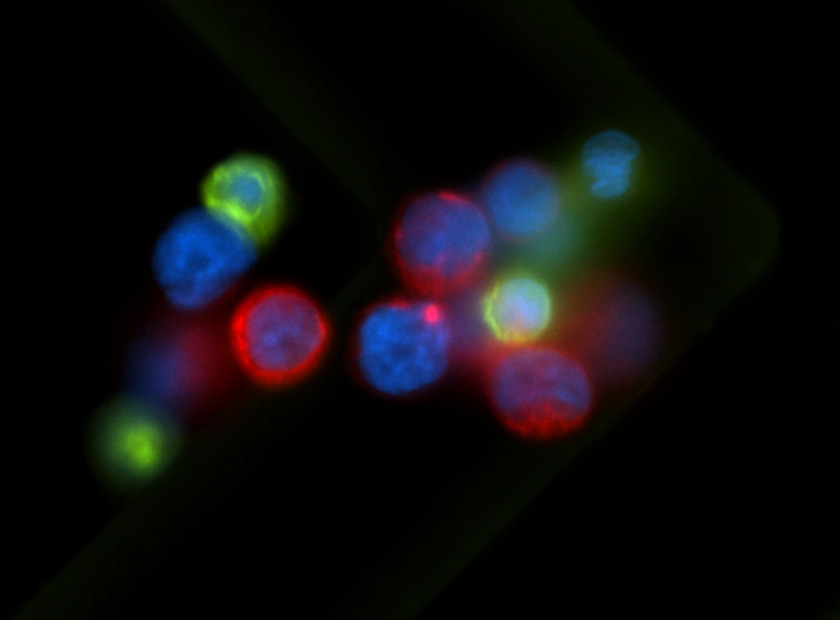

Distant metastasis is mostly initiated by tumor cells shed from the primary tumor into the blood circulation, known as circulating tumor cells (CTCs). Not all CTCs survive the harsh environment of circulation, but those that survive are carried to distant organs where metastatic tumors eventually arise. Advances in technologies have allowed us to be able to isolate CTCs from cancer patients. However, their biological properties which promote their survival and metastatic potential are still largely undefined. Our lab is interested in identifying the metastasis-initiating cells from the CTCs populations in patients and developing new therapeutic approaches for targeting them. The lab research focuses on two major topics: tumor intrinsic properties of CTCs that are capable of initiating metastasis and associated tumor extrinsic microenvironmental regulation which promotes this metastasis-initiating potential.

CTCs experience unique environmental stresses that could exhibit metastatic vulnerabilities. We combine transcriptional and epigenetic profiling with phenotypic investigations to elucidate the underlying mechanisms associated with context dependent role of nuclear receptors and signaling.

The hypoxia niche could impact metastatic capacity of the exited CTCs. We are investigating the long-term effect of hypoxia, termed “hypoxic memory”, and its associated molecular mechanisms as related to breast cancer metastasis.